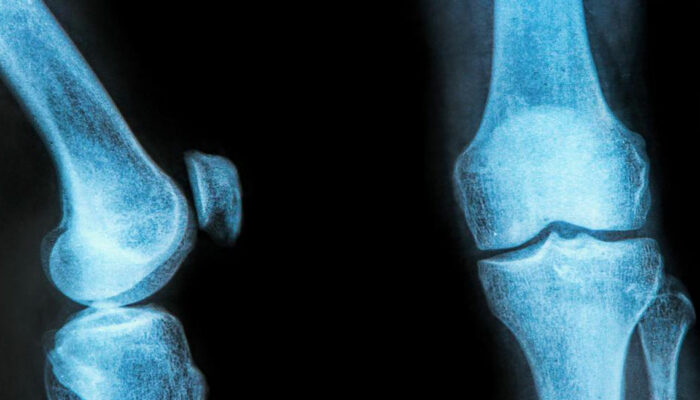

The rubbery C-shaped disc cushioning your knee is a meniscus. There are two menisci in each knee. One at the inner side and the other on the outer side. It is this meniscus that helps to keep your knee steady. It balances your body weight around your knee. If there is a tear in the meniscus, you will experience a lot of pain.

You can distinguish the types of meniscus tear based on its symptoms. The types can range from being minor to more severe tear. A minor tear involves a slight swelling of the knee and can last up to 2 to 3 weeks. If the swelling has aggravated after a sudden twist or turn, you might be experiencing a partial tear. In this regard, a moderate medial or lateral meniscus tear brace can ease the pain.

In the case of a moderate tear, the pain lies in the center of the knee. The swelling is visible over 1 or 2 days. In this case, walking is possible, but the bending of the knee might cause stiffness. The symptoms arrive and withdraw over a prolonged period. They can cause enough trouble unless treated at the right time. A meniscus tear brace with two sturdy aluminum uprights and bilateral hinges will be beneficial in the case of a moderate tear.

A severe tear is considered as an extreme case. A severe tear tends to happen when the meniscus flows into the knee joint area. You will find it difficult to walk, bend, or turn your knee. You might feel that your knee seems locked up. Sometimes, the swelling returns after 2 to 3 days of the injury. So, often you might not even realize that you suffer from a meniscus tear. A thigh and calf strap will help to compress the knee joint, effectively relieving the pain.